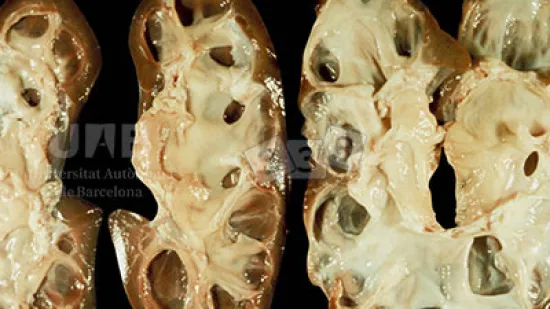

Semaine du 25-Jul-2022

Quelle est la lésion rencontrée en sectionnant la cavité nasale d’un porc de 10 semaines d’âge ?